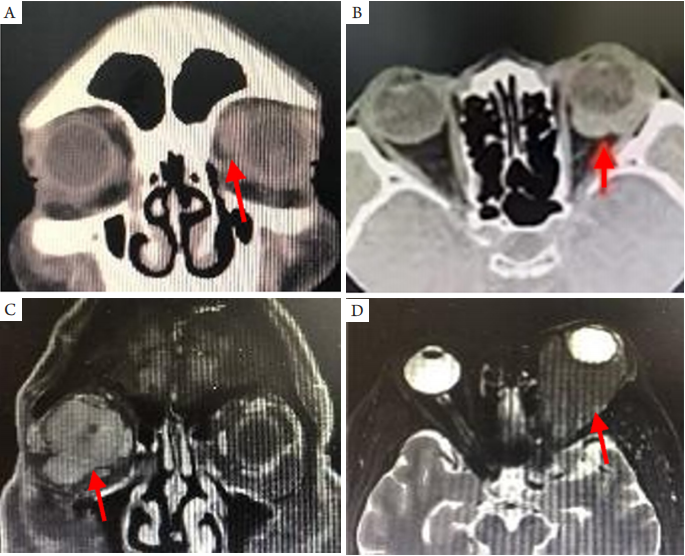

原发于泪囊和鼻泪管的淋巴瘤罕见,最常见的病理类型为MALT淋巴瘤和弥漫大B淋巴瘤。常见症状是溢泪、泪囊区肿胀、泪囊区肿块和泪囊炎症;体征是泪囊区可触及肿块和冲洗显示泪囊阻塞[19-20]。CT显示泪囊区或/和鼻泪管高密度占位、合并鼻泪管扩张增粗;MRI显示泪囊和鼻泪管病变T1WI和T2WI均为等信号(图4)。原发性泪道MALT淋巴瘤亦可见于儿童[21],临床应予重视。

20230619102640_9581.png

图4 泪囊和鼻泪管原发性MALT淋巴瘤的MRI表现

Figure 4 MRI findings of Primary MALT lymphoma in the dacryocyst and duct

(A)T1WI显示右泪囊区等信号占位;(B)T2WI显示右鼻泪管增宽,占位病变呈等信号。箭头示病变部位。

(A) Axial MRI shows the mass with isosignal in T1WI in the lacrimal sac area; (B) Coronal MRI shows the mass with isosignal in T2WI in the lacrimal duct. Arrows indicate the lession.